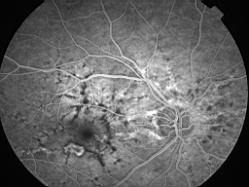

ASSOCIATION STRIES ANGIOIDES ET DYSROPHIE MACULAIRE RETICULEE

NEOVASCULARISATION